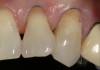

Before bonding, the enamel was etched with 37% phosphoric acid (ETCH-37™ 37% Phosphoric Acid Etchant, BISCO, Inc., www.bisco.com). A dentinal adhesive (ALL-BOND UNIVERSAL®, BISCO, Inc.) was placed, blown thin for 10 seconds with forceful compressed air, and then light-cured for 20 seconds (Figure 4). Using an injectable composite resin (G-ænial Universal Flo), a sequence of composite resin layering was performed to blend the composite resin to the existing tooth and create a natural polychromatic effect. To match the chromaticity along the gingival area, an opacious dentin shade, AO2, was bonded over the RMGI to mimic the lost dentin (Figure 5). Using a free-hand sculpt technique, universal shade A2 was injected over the opacious dentin composite resin with an emphasis on placing a convex anatomy to simulate natural dentition. Because of the chameleon effect and the depth of color of the body shade A2, no other shades were needed (Figure 6).

After final light-curing, esthetic contours were refined using aluminum oxide finishing discs (Sof-Lex™ Finishing Disc, 3M ESPE, www.3mespe.com) and Q-Finisher® composite resin finishing burs (H50AQ, Komet USA). Finally, microdiamond-infused polishing wheels and 1.0-µm microdiamond polishing paste brought out the surface luster of this injectable composite resin (Figure 7 and Figure 8). Using proper technique and state-of-the-art dental materials, natural color, contour, and finish to mimic tooth were achieved.12